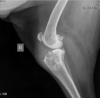

Describe the elbow joint on radiography.

53

elbow mediolateral in flexion, you can spot what 3 pathologies:

- ununited anconeal process - osteophytes - flexor enthesopathy